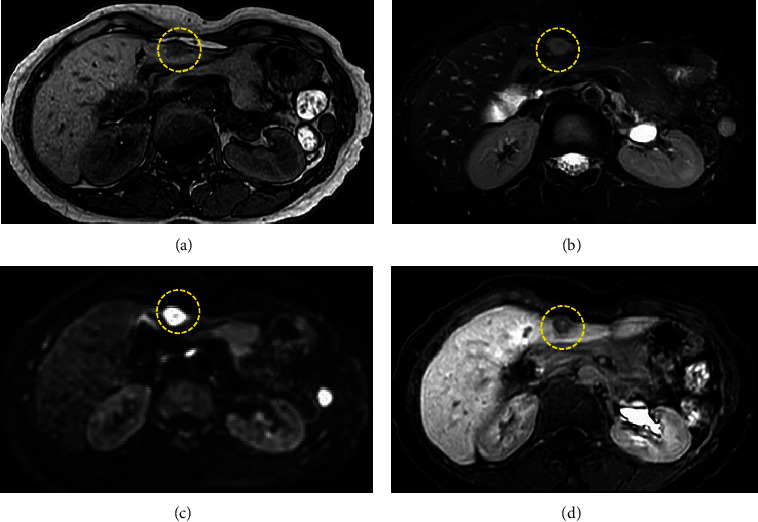

反应性淋巴细胞增生(RLH)是一种良性疾病,很少发生在肝脏。有报告称,反应性免疫现象与该病的发生有关,但真正的发病机制尚不清楚。目前还没有与炎症性肠病相关的病例报道。我们报告了一例溃疡性结肠炎(UC)患者的肝脏 RLH 病例。一名 55 岁的 UC 女性患者因腹痛前往门诊就诊,医生诊断为急性阑尾炎,并开了抗生素。影像学检查发现肝脏有肿块,但排除了阑尾炎的可能。疼痛好转后,她被转到我院接受进一步检查。超声波检查发现肝脏内有一个 12 毫米的低回声肿块。计算机断层扫描和磁共振成像没有发现典型的恶性病变。医生建议定期进行影像随访,但患者强烈要求手术治疗,因为他有家族恶性疾病史。患者接受了腹腔镜肝部分切除术。组织病理学检查结果显示,淋巴滤泡呈聚集性增生,并伴有生发中心。浸润的淋巴细胞未见新生物。最终诊断为肝脏 RLH。UC 是一种慢性炎症性肠病,可能与 RLH 有关,但目前尚无明确的解释。这是已知的首例 UC 患者肝脏 RLH 病例。但 RLH 与 UC 之间的关系仍不确定。有必要进行进一步的调查和病例积累。

Reactive lymphoid hyperplasia (RLH) is a benign disease, rarely occurring in the liver. Reactive immune phenomenon has been reported in association with its occurrence, but the true pathogenesis is unknown. No case was reported in association with inflammatory bowel disease. We report a case of RLH of the liver in a patient with ulcerative colitis (UC). A 55-year-old woman with UC went to the outpatient clinic with abdominal pain, and antibiotics were prescribed with diagnosis of acute appendicitis. Imaging study detected a mass in the liver but ruled out appendicitis. She was referred to our hospital for further examination after pain improving. A 12 mm hypoechoic mass was detected in the liver on ultrasonography. There were no typical malignant findings on computed tomography and magnetic resonance imaging. Regular image follow-up was recommended, but the patient strongly requested surgery because of family history of malignant disease. Laparoscopic partial hepatectomy was performed. Histopathological findings revealed a conglomerate hyperplasia of lymphoid follicles with germinal centers. Infiltrating lymphocytes were non-neoplastic. Final diagnosis was RLH of the liver. UC is chronic inflammatory bowel disease and may be related to RLH, but there is no clear explanation at this point. This is the first known reported case of RLH of the liver in a patient with UC. But the relationship between the RLH and UC remains uncertain. Further investigation and case accumulation are necessary.